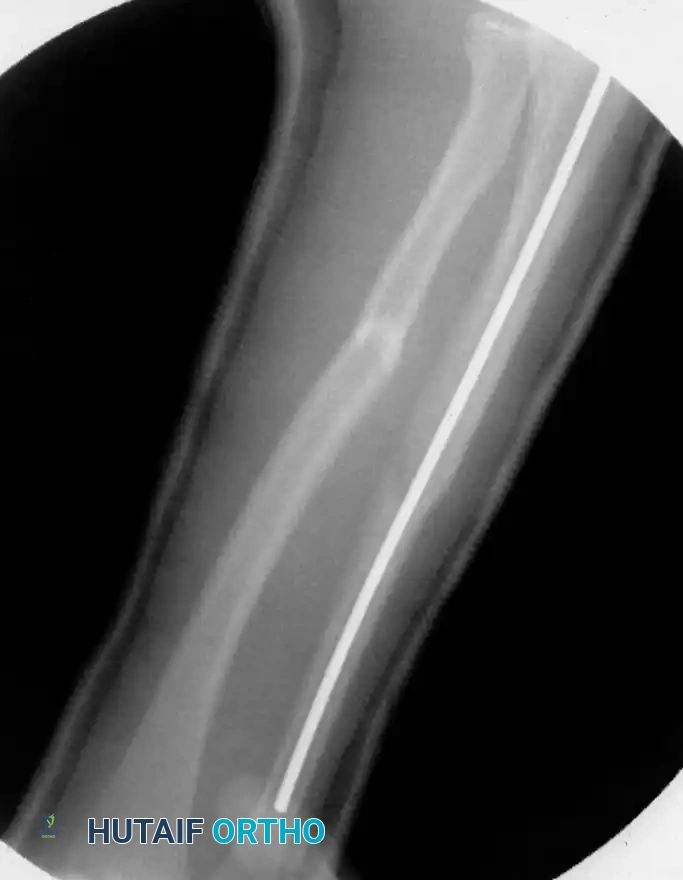

2. Elastic Stable Intramedullary Nailing (ESIN)

ESIN has become the gold standard for displaced, unstable pediatric forearm fractures. Lascombes et al. and Flynn and Waters popularized this technique, citing minimal soft-tissue dissection, preservation of the fracture hematoma, and the ability to achieve three-point biomechanical fixation.

Image

Preoperative Planning:

Nail diameter should be approximately 40% of the narrowest intramedullary canal diameter. Titanium elastic nails (TENs) are preferred for their modulus of elasticity.

Step-by-Step Surgical Technique:

1. Positioning: The patient is placed supine with the arm extended on a radiolucent hand table. Fluoroscopy is positioned perpendicular to the arm.

2. Ulnar Nailing:

* An incision is made over the lateral aspect of the proximal ulna, 1-2 cm distal to the olecranon apophysis.

* The cortex is breached with an awl or drill.

* The pre-bent nail (contoured to create a bow that will tension against the inner cortices) is advanced antegrade down the ulnar shaft to the fracture site.

3. Radial Nailing:

* An incision is made laterally over the distal radius metaphysis, carefully avoiding the superficial branch of the radial nerve and the physis.

* The entry point is created, and the pre-bent nail is advanced retrograde.

4. Fracture Reduction and Nail Passage:

* Closed reduction is performed. The nails are advanced across the fracture sites under fluoroscopic guidance.

* If closed reduction is impossible due to interposition (often seen when initial translation exceeds 100%), a mini-open incision (1-2 cm) is made directly over the fracture to clear the soft tissue.

5. Final Seating: The nails are advanced to the opposite metaphyses. The trailing ends are cut, leaving 1-2 cm outside the bone but buried beneath the skin to facilitate future removal.